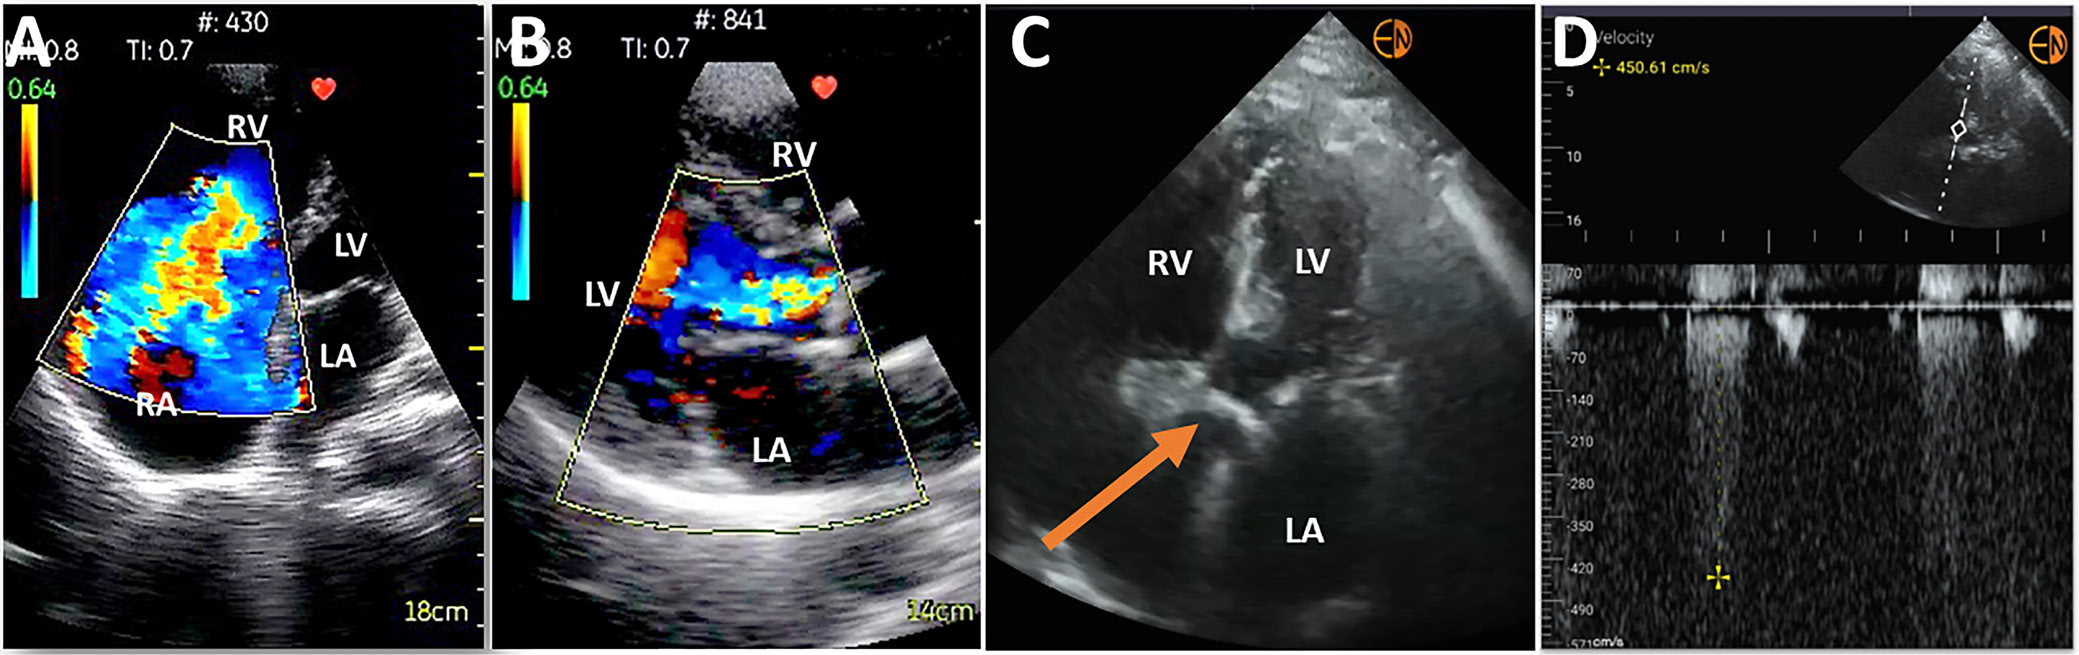

Right ventricle (RV) visualization with HUDs proves more challenging. Variable correlations between HUD and high-end systems to identify RV dysfunction have been reported. Some studies showed that HUDs proved feasible in the initial assessment of patients with suspected pulmonary embolism. It was concluded that rapid imaging protocols with HUDs, based, among others, on RV enlargement, allow for improved initial evaluation of patients with suspected pulmonary embolism and increase the diagnostic accuracy of clinical risk assessment scores (Figure 2).15, 16

Initially, a valvular assessment could only be qualitative and based on the visual detection of morphologic abnormalities, such as significant calcification or dilated valvular ring. Due to the introduction of the color Doppler modality, such assessment, although still qualitative, became more accurate. Quantitative analysis was recently made available with the implementation of spectral Doppler to a HUD. It was already confirmed that experienced operators can reliably detect clinically significant aortic stenosis (AS) and facilitate AS grading with the use of this HUD, and this modality might prove promising (Figure 3).21